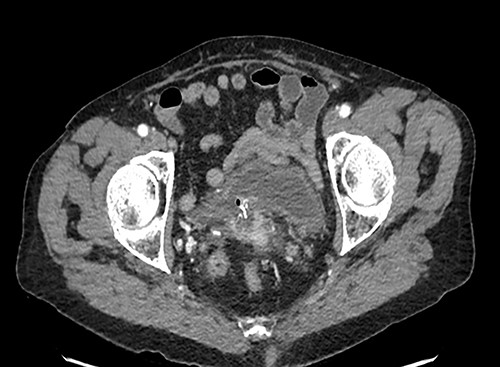

A 42-year-old woman was admitted to our unit with vaginal discharge for 1 month. She had previously undergone an open anterior mesh rectopexy for complete rectal prolapse in 1997; she also had a history of mesenteric ischemia with an extensive intestinal resection in 2005. Vaginal examination showed the polypropylene mesh protruding out through the bottom of the vagina. Digital rectal examination was normal. CT scan showed an infection with an abscess of the rectopexy mesh, inflammation and infiltration next to the lower rectum and the anorectal junction fusing into the right ischioanal fossa. It also showed a vaginal fistula at the level of the posterior vaginal fornix, with an exposure of the mesh at this level. Under general anesthesia in gynecologic position, a sub-total removal of the mesh was done using a transvaginal approach. The postoperative outcomes were uneventful.

CT scan of abdomen and pelvis with contrast helps in localizing the mesh as well as the presence of any pelvic collection, severity of inflammation around the area of mesh and erosion into adjacent viscera [2].